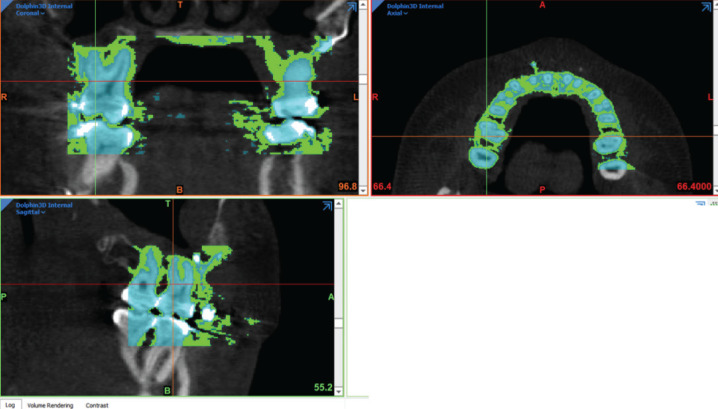

Methods: Eighteen subjects, aged 18 to 65 years with pre-surgery (T0), post-surgery (T1), and long-term follow-up (T2) CBCT records were included. Sixteen control subjects, aged 17.67 to 62.33 years, with pre-treatment (T0), progress (T1), and long-term progress orthodontic (T2) CBCT records were also used. Maxillary central incisor, canine, and first molar roots were segmented. The volume, surface area, and root length changes were analyzed using repeated measures ANOVA and mean differences across follow-up periods. Significance was set at p<0.05.

Abstract Image